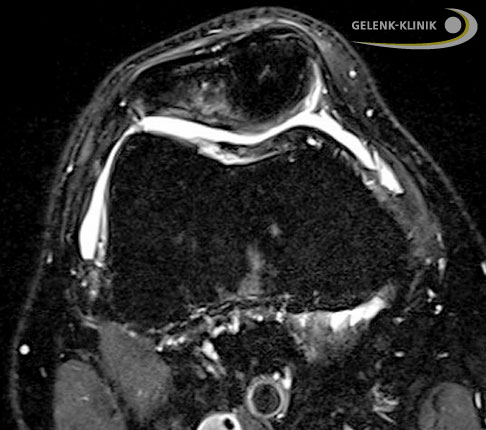

Knorpelschaden im Kniegelenk, seitlich Seitliche MRT-Aufnahme eines Knorpelschadens im Kniegelenk. Der Knorpelschaden erscheint weiss in dem ansonsten homogenen hellgrauen Bereich (gesunder Knorpel) an der Rückfläche der Kniescheibe. © Gelenk-Klinik Knorpelschaden im Kniegelenk, quer Als Folge des Knorpelschadens hat sich zusätzlich eine Flüssigkeitsansammlung im Knochen der Kniescheibe (Patella) gebildet. Das Knochenödem stellt sich als aufgehellter Bereich oben im MRT-Bild dar. © Gelenk-Klinik